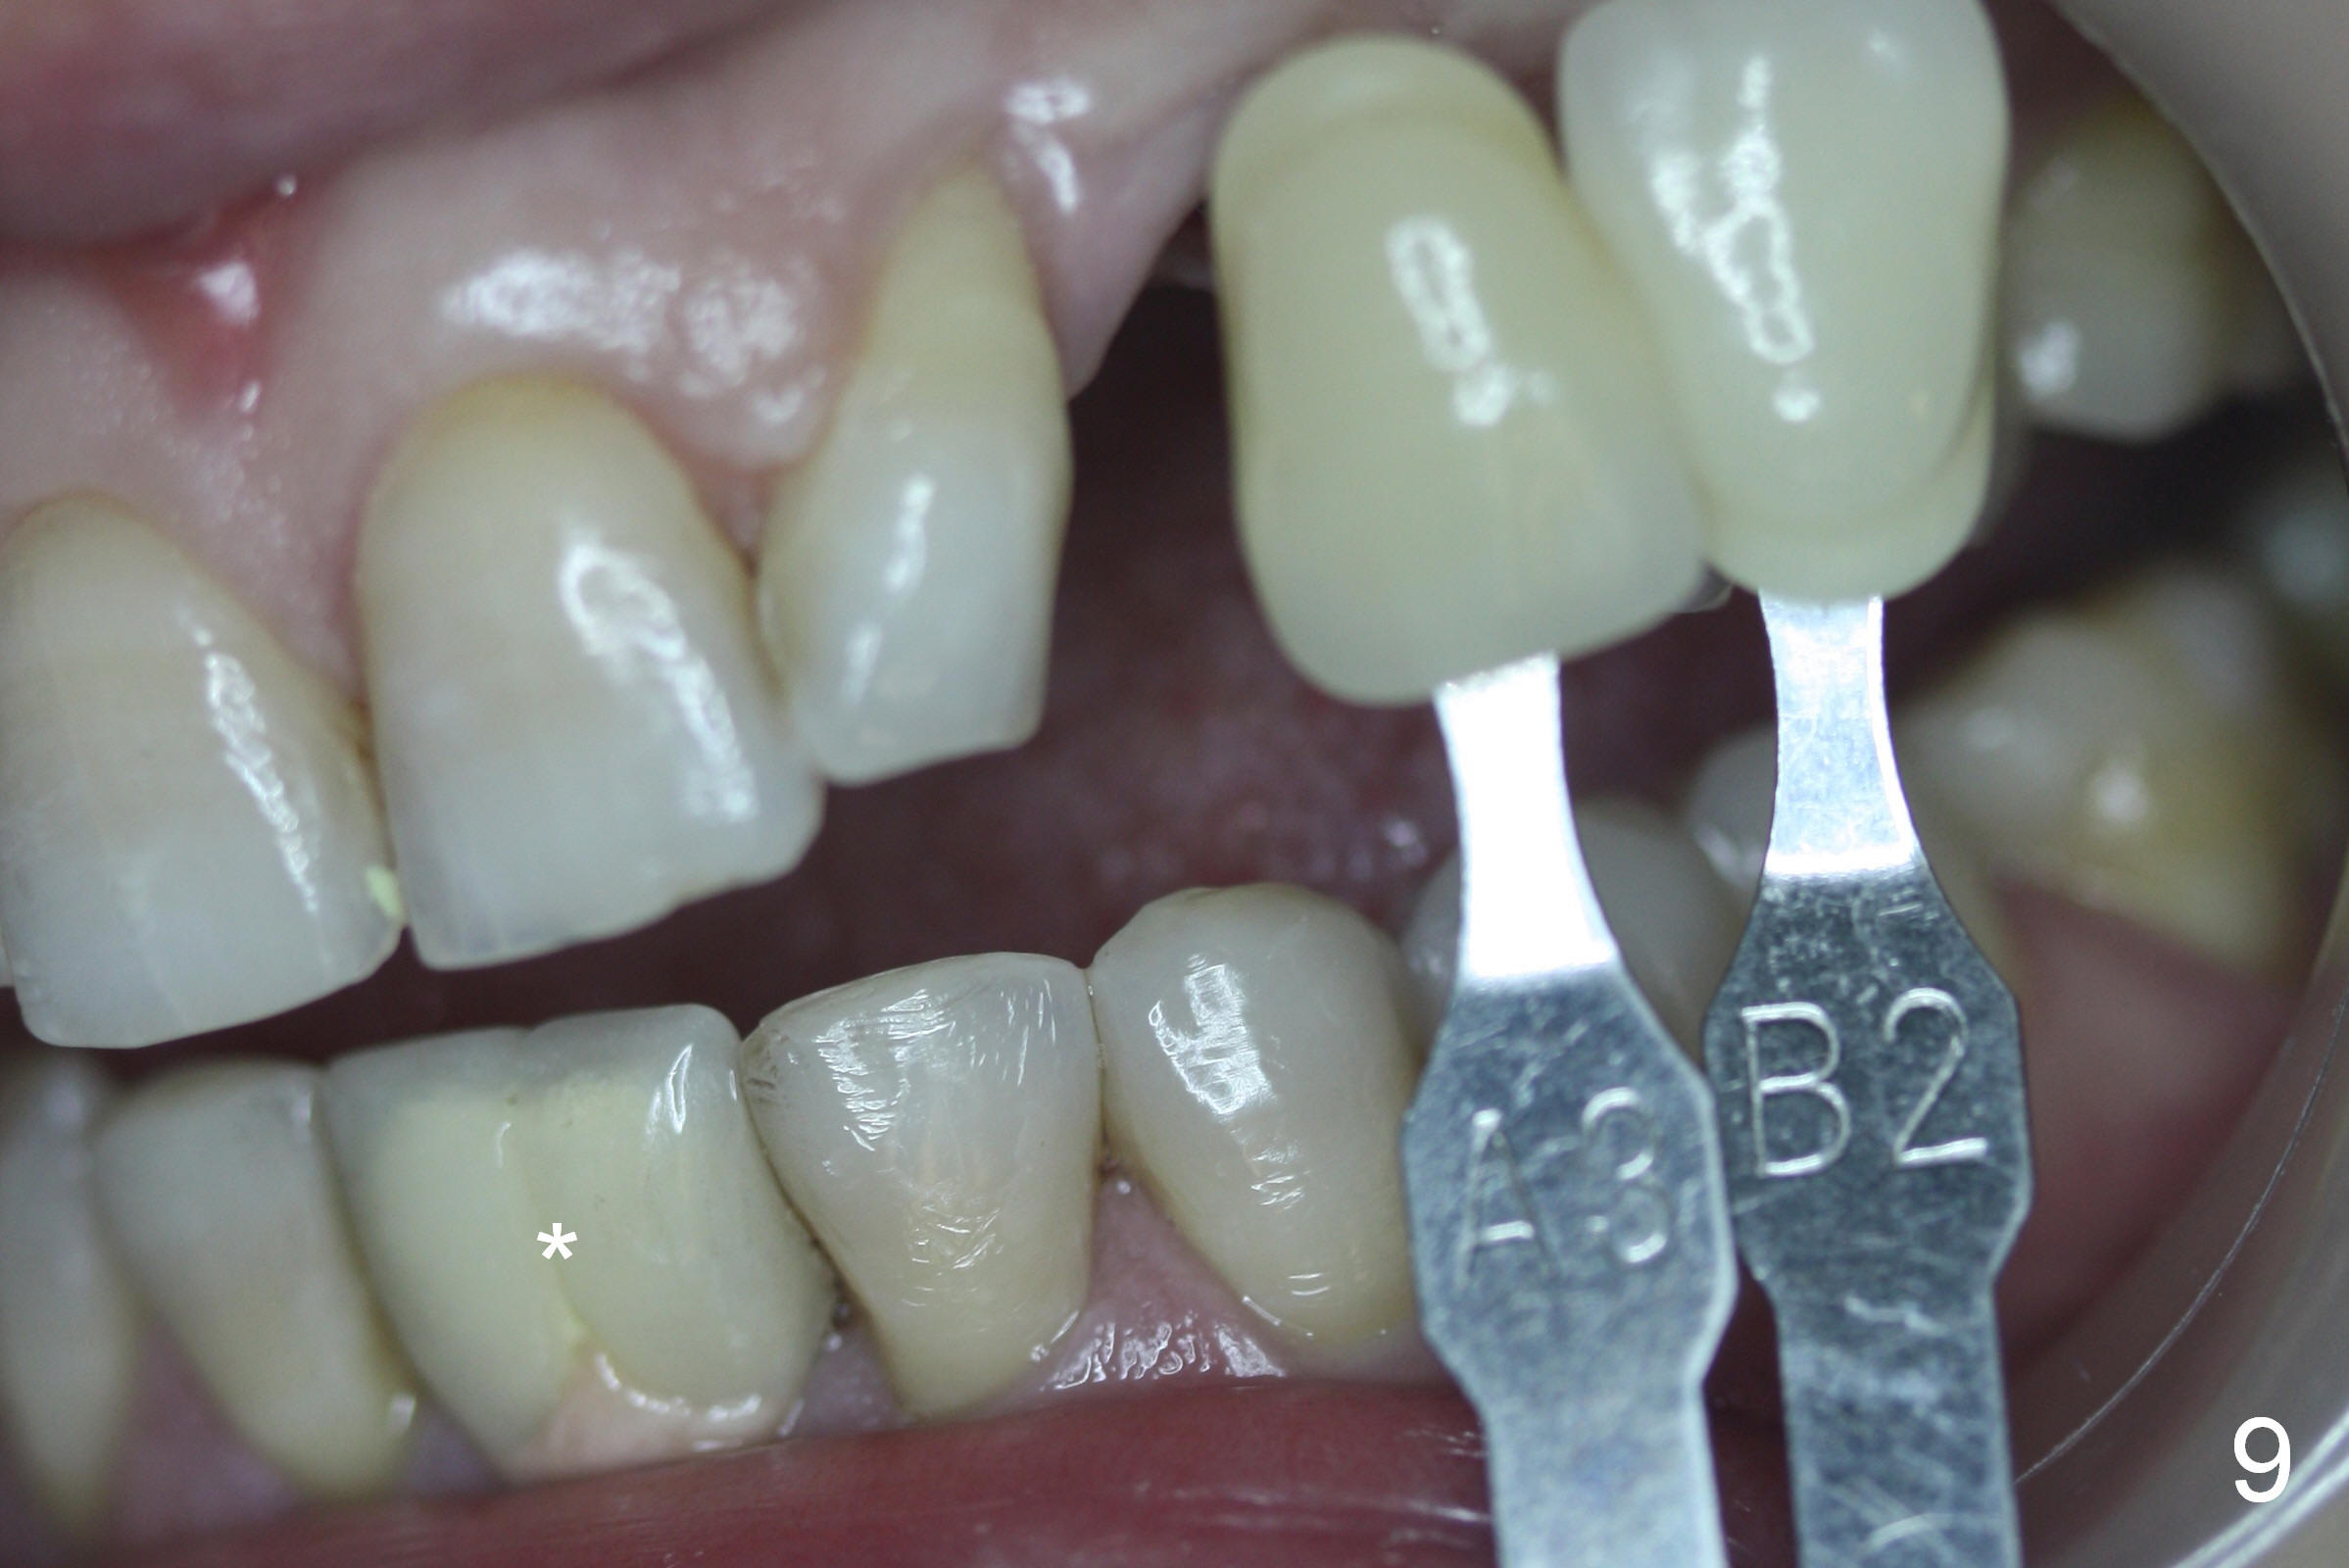

The ridge looks wide clinically 4 months post implant removal and socket preservation. In fact, the graft bone is soft and the ridge is narrow after incision. It appears that an angled 1 piece implant is an indication. A 1.2 mm pilot drill is used to start osteotomy. At approximately 17 mm, the patient feels pain. The nasal floor perforates? A 2 mm osteotome is utilized to enlarge the osteotomy. At 17 mm, the osteotome is stable (Fig.1), but the nasal floor appears out of view. Review of the preop PA shows that the distance between the gingival margin and the nasal floor (arrowheads) is ~22 mm (Fig.2). It should be safe and necessary to place a 3x20 mm 1-piece implant with 15° angulation. Insertion torque is between 40 and 45 Ncm.

Eight months postop, the patient returns for #11 restoration. She reports no problem at #11, while there is light tenderness with a 2-piece implant (4.5x20 mm) at #6 at night (Fig.10, a portion of panoramic X-ray). Clinical exam reveals no abnormality at #6. Although the implant at #11 is buccally placed, there is no buccal plate atrophy (Fig.6,7). In fact the 20 mm 1-piece implant is placed in the bone (septum) between the nasal cavity (Fig.10 pink dashed line; Fig.13 (CBCT (52 year-old lady) N) and the maxillary sinus (yellow dashed line, S). In fact the apparent nasal floor indicated as arrowheads in Fig.2 and 10 is the horizontal plate of the palatine bone (hard palate)! Therefore there is no nasal floor perforation in this case. A long implant is indicated in the upper canine.

The main reason for the failure of this case is buccal placement of the implant (Fig.11 A: abutment). Every time an implant is placed at the upper anterior, make sure that palatal placement is done (Fig.12 *). The most critical step is the 1st pilot drill. If the position is not ideal, use a Lindemann bur for adjustment. Check repeatedly. If the implant starts to be deviated buccally, remove the implant, use the Lindemann bur to remove more of the palatal bone and place the implant palatally.